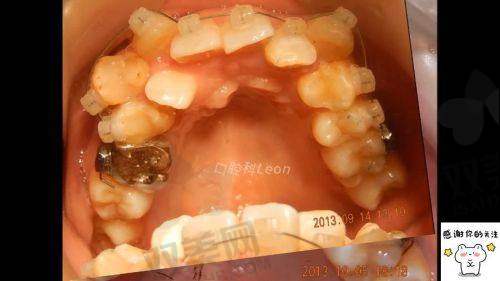

北京禾禾口腔门诊部擅长的项目是口腔正畸!在口腔正畸方面,门诊部可以为患者提供传统金属托槽矫正、陶瓷托槽矫正、隐形矫正等多种矫正方式,满足不同患者的需求。